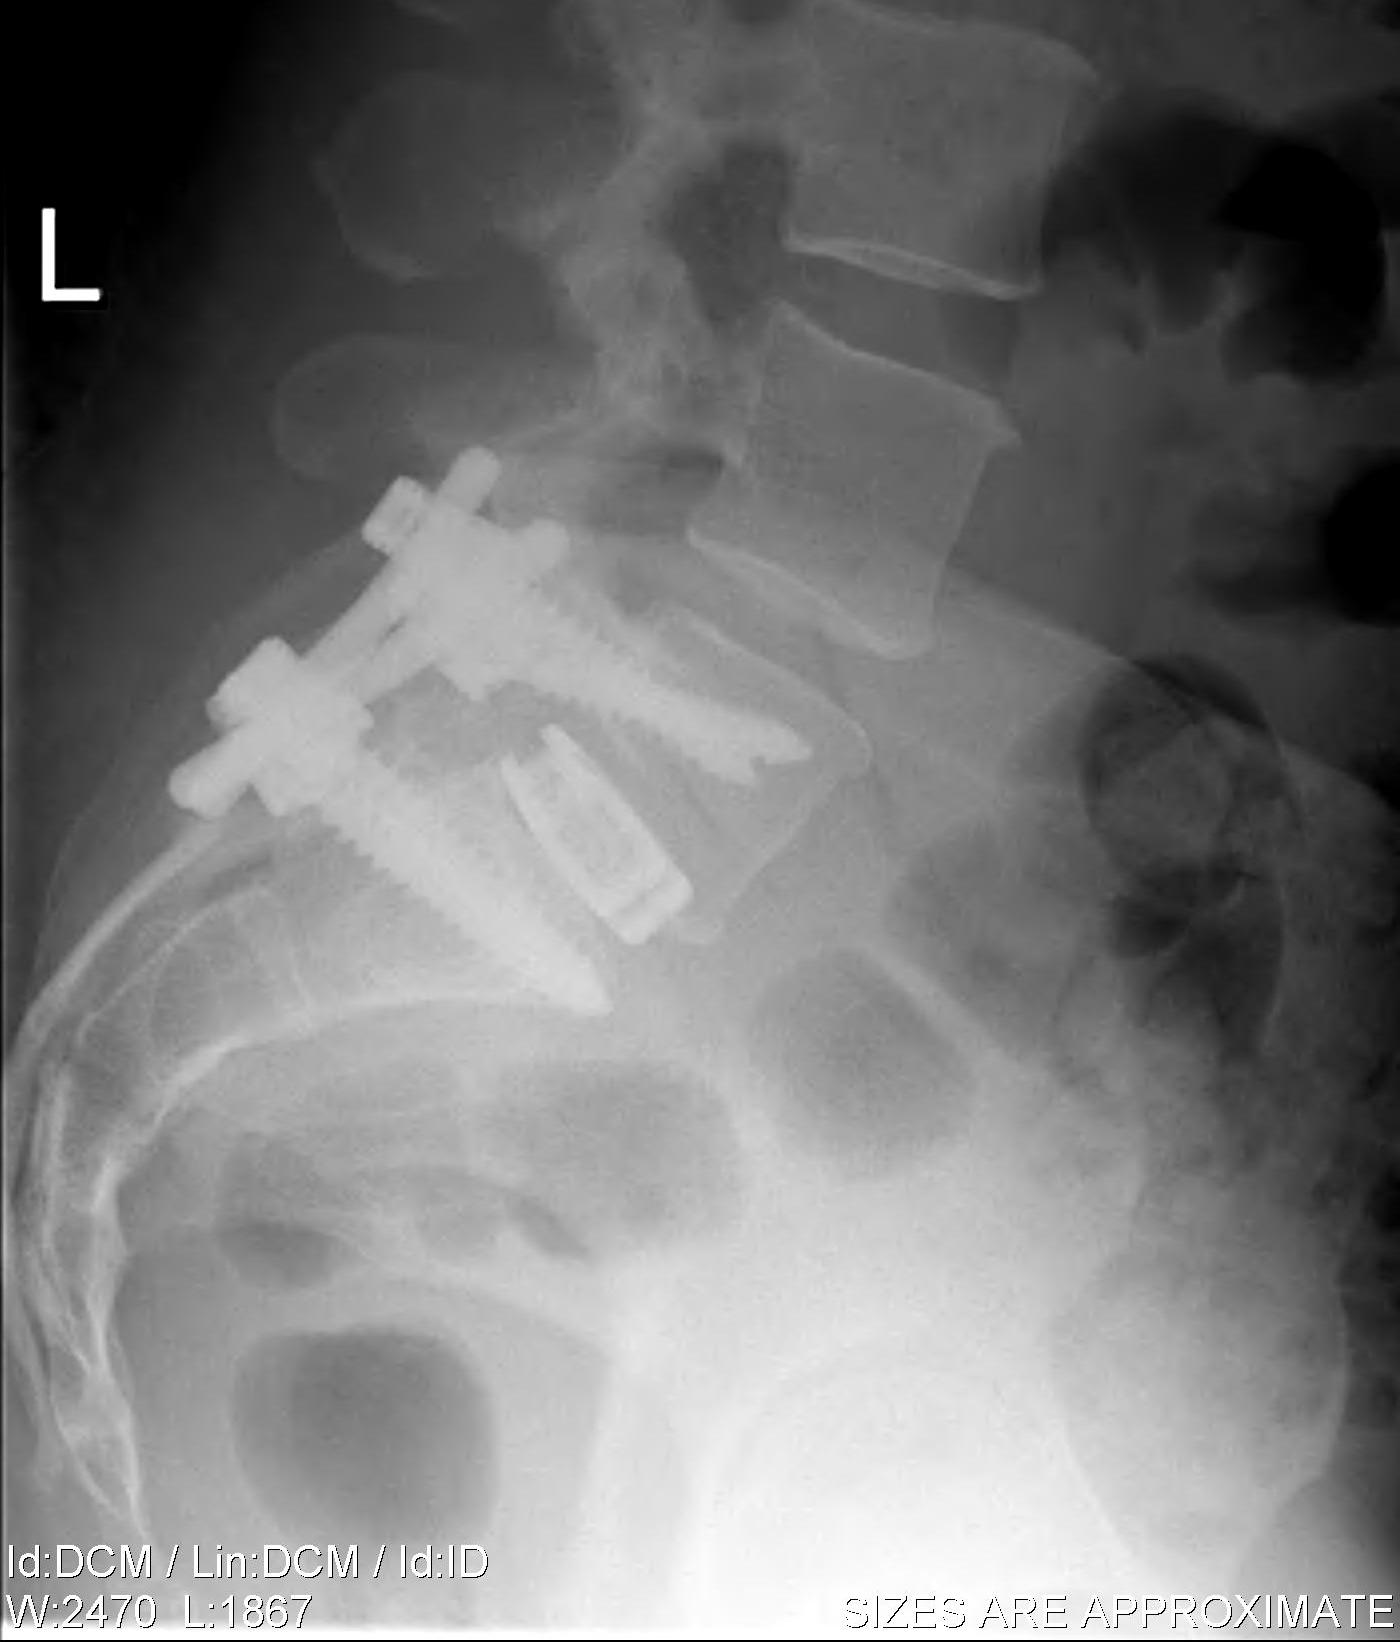

1. PLF / Posterolateral Fusion +/- instrumentation

2. Instrumented PLIF / Posterolateral Interbody Fusion

PFL

Concept

- decortication of pedicles / lamina / transverse process

- bone graft applied

- instrumentation added to improve fusion rate

Instrumented PLIF

Principles

- wide post decompression and removal of entire disc

- graft / fusion cage placed between vertebral bodies

- 360o fusion (PLF + interbody)